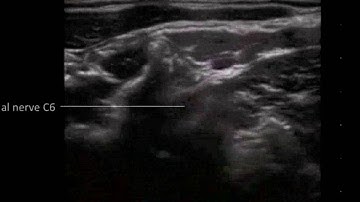

Cevical Plexus Nerve Block